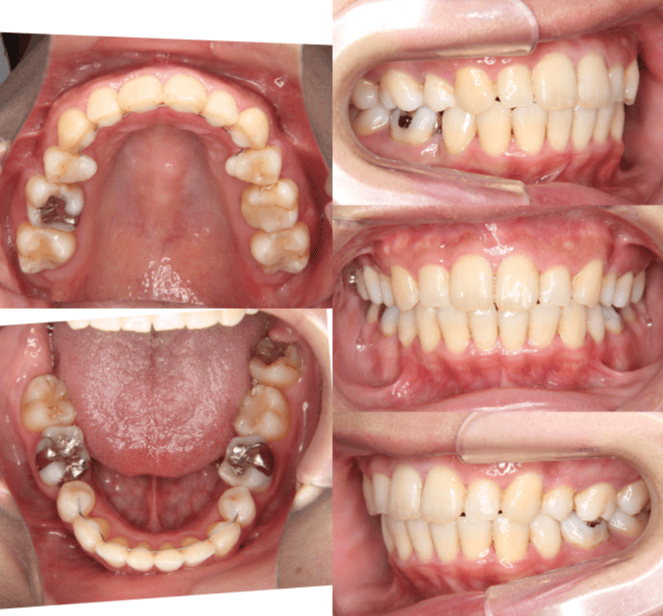

| 年齢・性別 | 25歳女性 |

|---|---|

| 主訴 | 前歯の歯並びの乱れ(叢生)を気にされて来院された25歳女性。咬み合わせや審美的な改善を希望されていました。 |

| 治療期間・回数 | 4年5ヶ月・30回 |

| 費用 | 1100,000円(税別) |